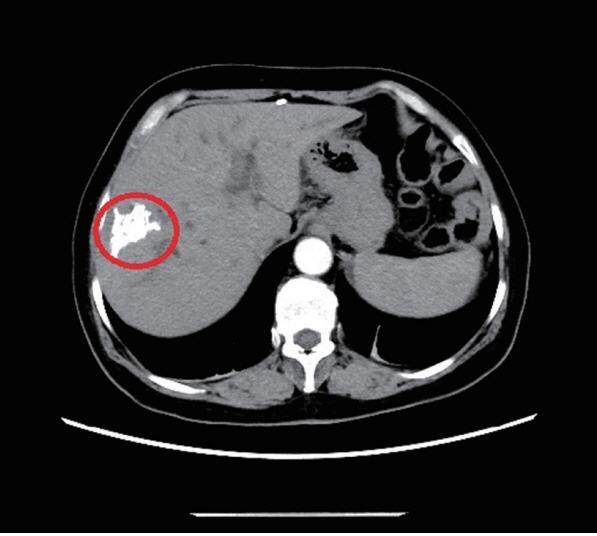

Fig. 1The abdominal and pelvic CT scan revealed that high-density nidi were scattered in the right lobe of the liver, approximately 42×22 mm (red ring marker site).